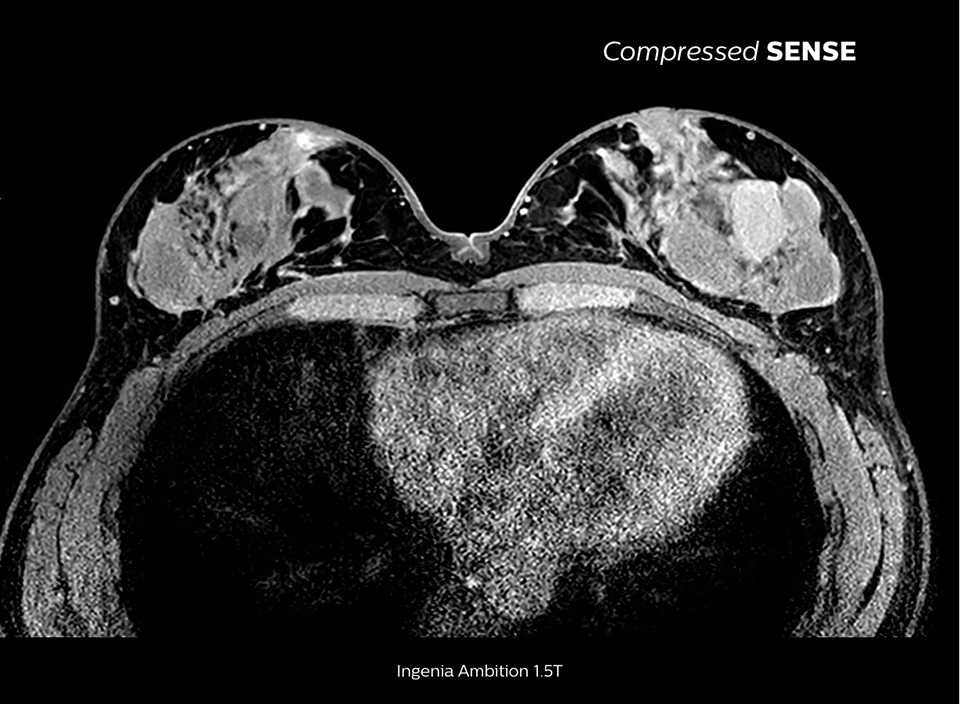

Scoprite i principi fondamentali del software RM Compressed SENSE e perché rappresenta un cambio di paradigma in fatto di produttività. Compressed SENSE è stato progettato pensando alla qualità dell'immagine e può accelerare le scansioni e migliorare la risoluzione spaziale e l'esperienza del paziente nell'imaging RM clinico.